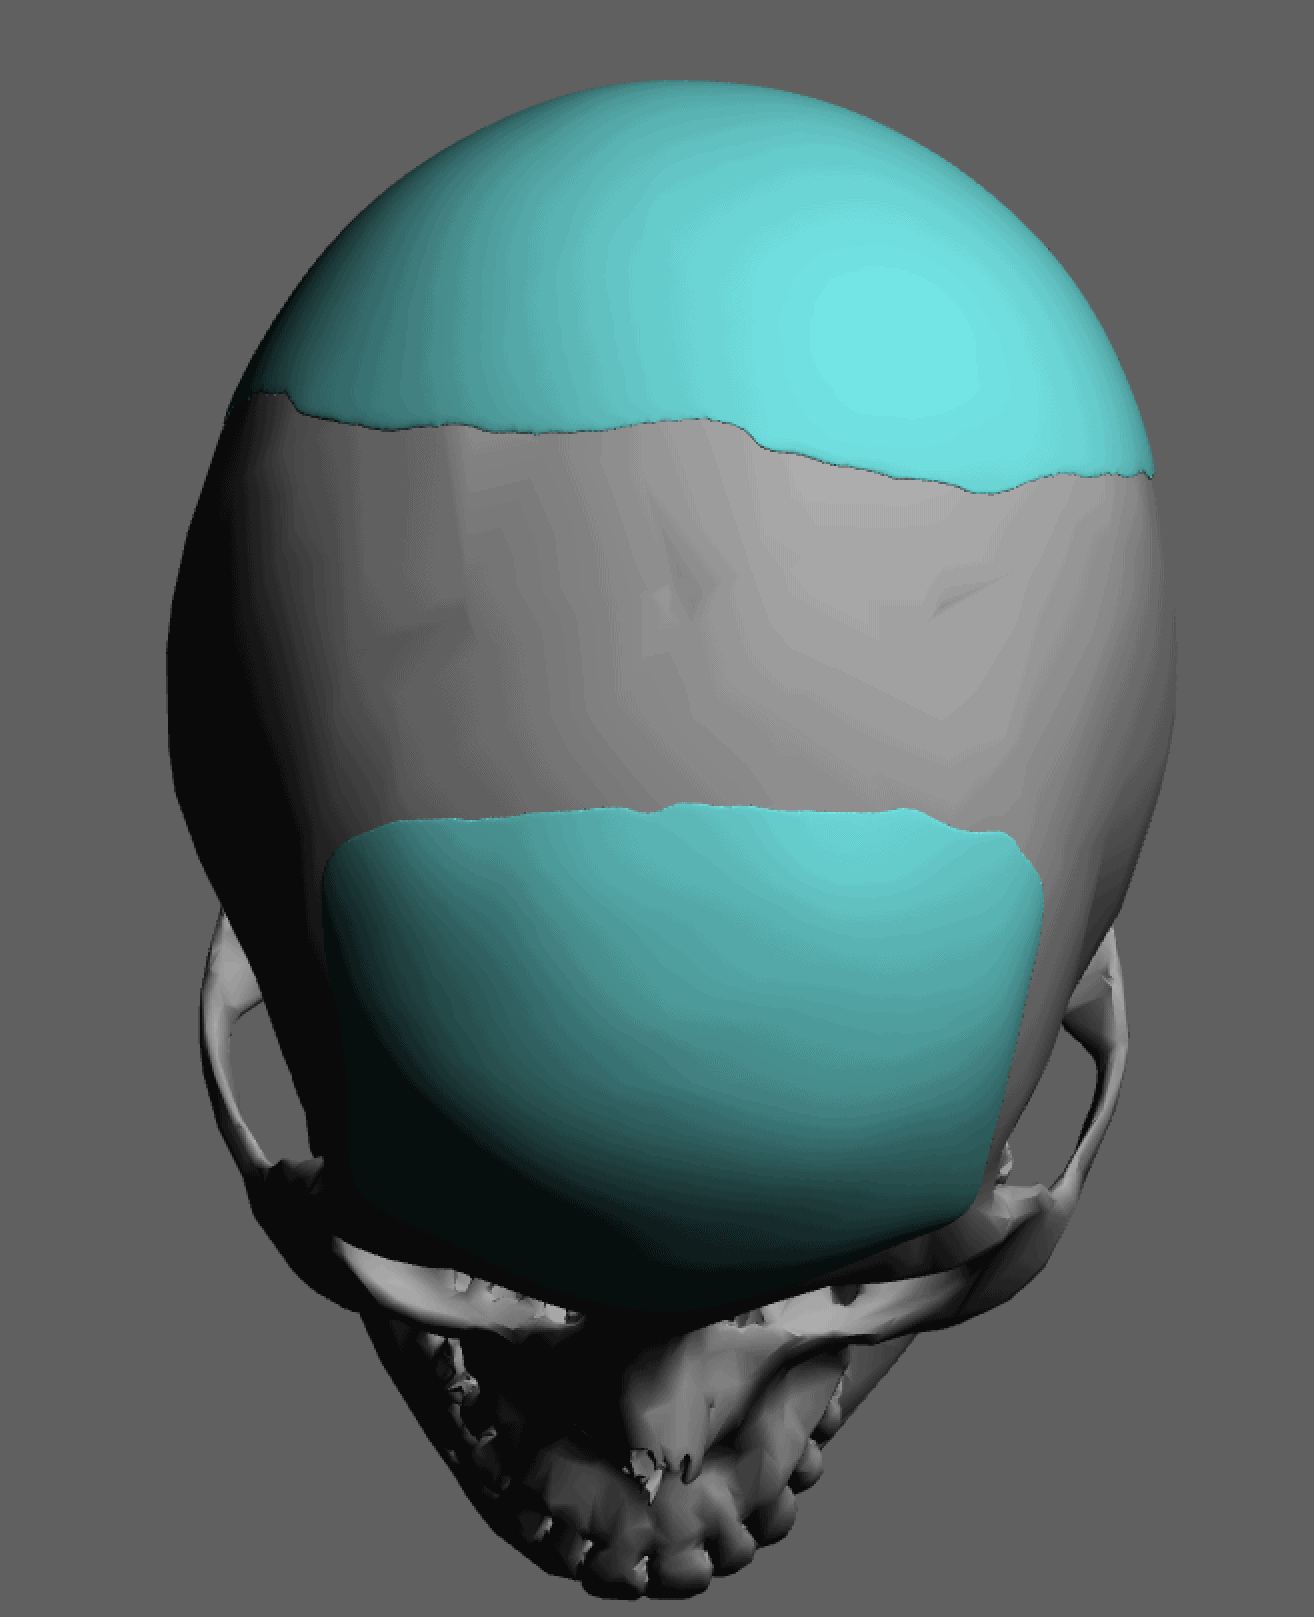

Severe narrowing skull deformity from prior sagittal craniosynostosis repair as an adult.

Complete replacement of entire skull by a custom implant with temporal fat injections.

Severe narrowing skull deformity from prior sagittal craniosynostosis repair as an adult.

Complete replacement of entire skull by a custom implant with temporal fat injections.